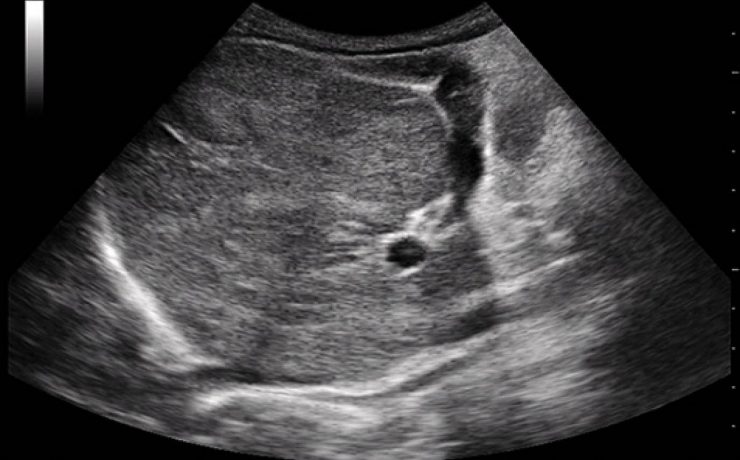

Escrito por Irene Arnanz González en 2014, hace la descripción de una paciente de 94 años quien ingresó a la consulta médica por prurito e ictericia con examen físico sospechoso por lo que se indicó ultrasonido de vías biliares con resultado de vesícula con pared gruesa de hasta 1cm de